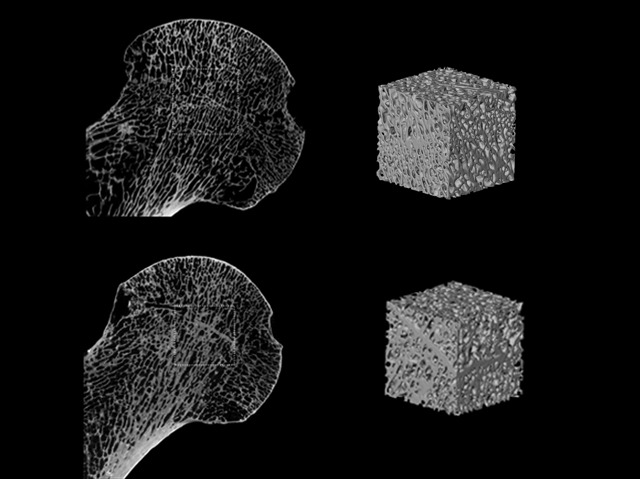

Nosaltres no seriem rivals amb els nostres avantpassats en la caça d'animals o la recollida de fruita en la copa dels arbres perquè els nostres ossos són més lleugers, més febles i més propensos a les fractures. Recents investigacions suggerixen que això no es deu a l'evolució o la dieta, sinó al sedentarisme –el que significa que podríem desenvolupar un esquelet igualment robust si posarem utilitzarem els ossos de la mateixa mesura. A la imatge apareixen dos fèmurs i cubs dels seus centres esponjos, que mostra que la densitat òssia –la quantitat de material blanc– va ser més gran en un recol·lector de fa 7.000 anys (a baix) que en un pagès de fa 1.000 anys (a dalt). La tendència cap a l'estil de vida més fàcil ha continuat des de llavors –i pot haver debilitat els ossos a un nivell crític, amb l'osteoporosi estesa en l'edat adulta. Aquesta investigació apunta fortament cap a l'exercici al llarg de la vida, en lloc de dietes i suplements alimentaris, en ser la millor solució.